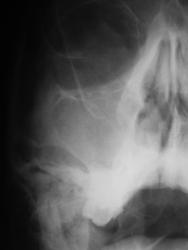

- https://radiomed.ru/sites/default/files/styles/case_slider_image/public/user/12/7.p..pc140012.jpg?itok=21Xz6ceG

Правосторонний гайморит и фронтит с тотальным снижением пневмотизации правой гайморовой и правой половины лобной пазух; в левой гайморовой пазухе - вероятно киста в альвеолярной бухте; пристеночное снижение воздушности левой половины лобной пазухи.

+1. Но в левой лобной "кругляшка" больше на остеомку тянет.

Правосторонний гайморит, этмоидит, фронтит. Слева киста в/челстной пазухи.

Кругляшок слева в лобной похож на остеому.